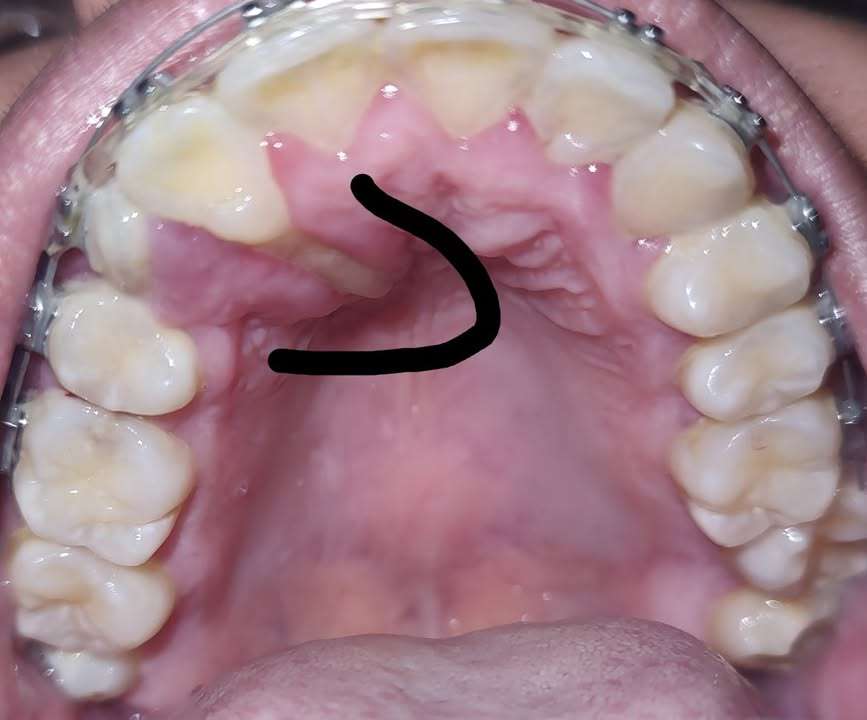

右上側切歯の歯根が口蓋側から露出している。

この歯はまあ抜歯するしかないんだろうなあと思われるような症例である。

つまり、右側に限局した犬歯の唇側転移で、片側的に小臼歯を抜歯して、犬歯をその部分まで移動したところ、側切歯の歯根が露出したということだろう。

おそらく、犬歯の歯根は、側切歯の歯根より近心にあり、側切歯の歯根はこれに押し出されるような格好で口蓋側に移動したものと思われる。

すでにこの側切歯は歯根が露出しているということで抜歯ということになるだろう。